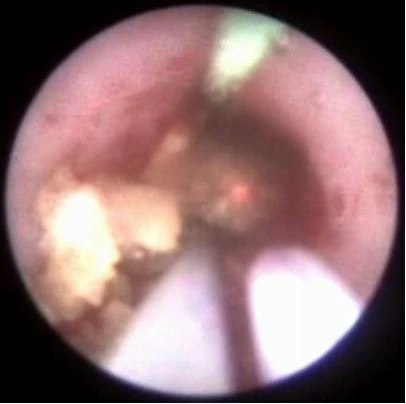

Через мочеиспускательный канал, в полость мочевого пузыря, вводится уретеропиелоскоп. Все манипуляции эндоскопическим инструментом, а особенно поступательное его продвижение по мочевым путям, должны проводиться под контролем зрения с тонко выверенной силовой нагрузкой, в случае потери эндоскопической картины возможно только одно направление движения инструмента - из пациента.

Через рабочий канал уретеропиелоскопа проводится лазерное волокно. По оптическому каналу изображение от эндоскопа передается на монитор. Волокно вплотную подводится к камню и при нажатии на педаль подаётся лазерное излучение, вследствие которого происходит деструкция камня.

Добившись нужной дисперсности фрагментов камня, их элиминируют корзинкой, либо другими видами экстракторов (петли, щипцы). Производится эндоскопическая ревизия мочеточника. Подтверждается полное удаление фрагментов камня. Уретеропиелоскоп удаляется.